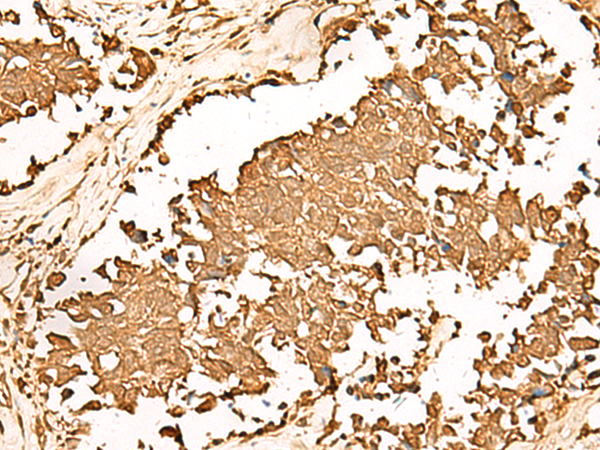

IHC positive control:

Human tonsil

IHC Recommend dilution:

50-300